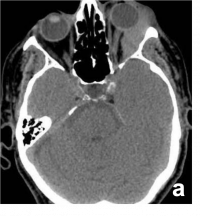

| Retinoblastoma[44] | Children | White reflex or strabismus. Most common intraocular tumor of childhood. | USG and MRI to distinguish RB from other causes of white reflex.

USG- evaluate calcification

CT- Radiation risk |

Retinoblastoma. a) Contrast-enhanced T1WI axial MRI image showing an enhancing right intraocular mass with no extraocular extension (orange arrow) b) T2WI axial MRI image showing hypointense signal (blue arrow) c) USG (B/A) showing intraocular mass lesion with specks of calcification corresponding to the spikes of A-scan. | |